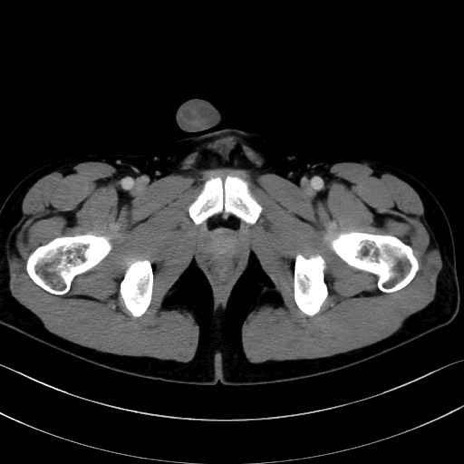

梨状筋(piriformis muscle) のCT画像の解剖

梨状筋 (Piriformis)

内閉鎖筋 (Obturator internus)